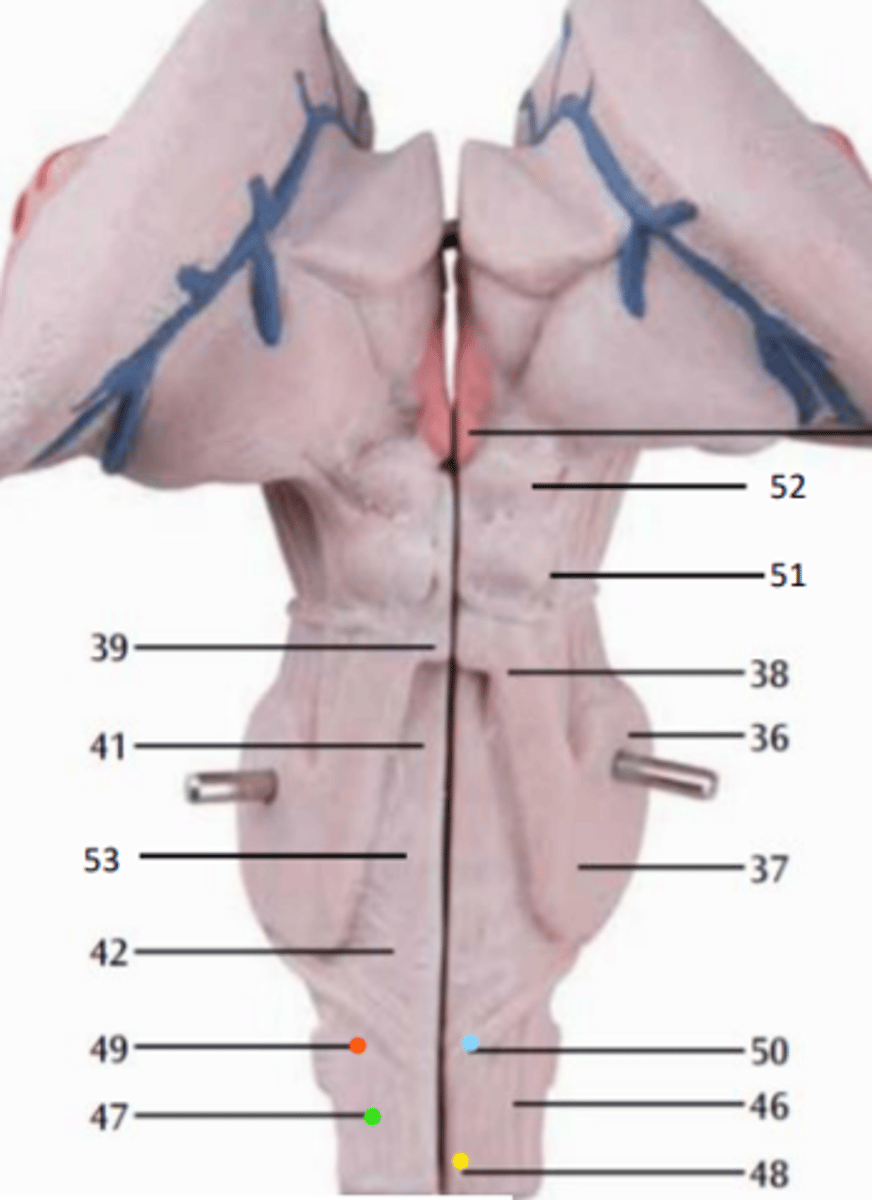

What is the blue arrow pointing at?

what is the blue arrow pointing to?

what structure is the blue pin in?

What is number 50 or the blue dot?

blue arrow is pointing to which structure?

The area the blue arrow is pointing to?

structure blue arrows are pointing to?

What area is the orange structure pointing to?

What area is the blue arrow pointing to?

Where is the yellow arrow pointing to?